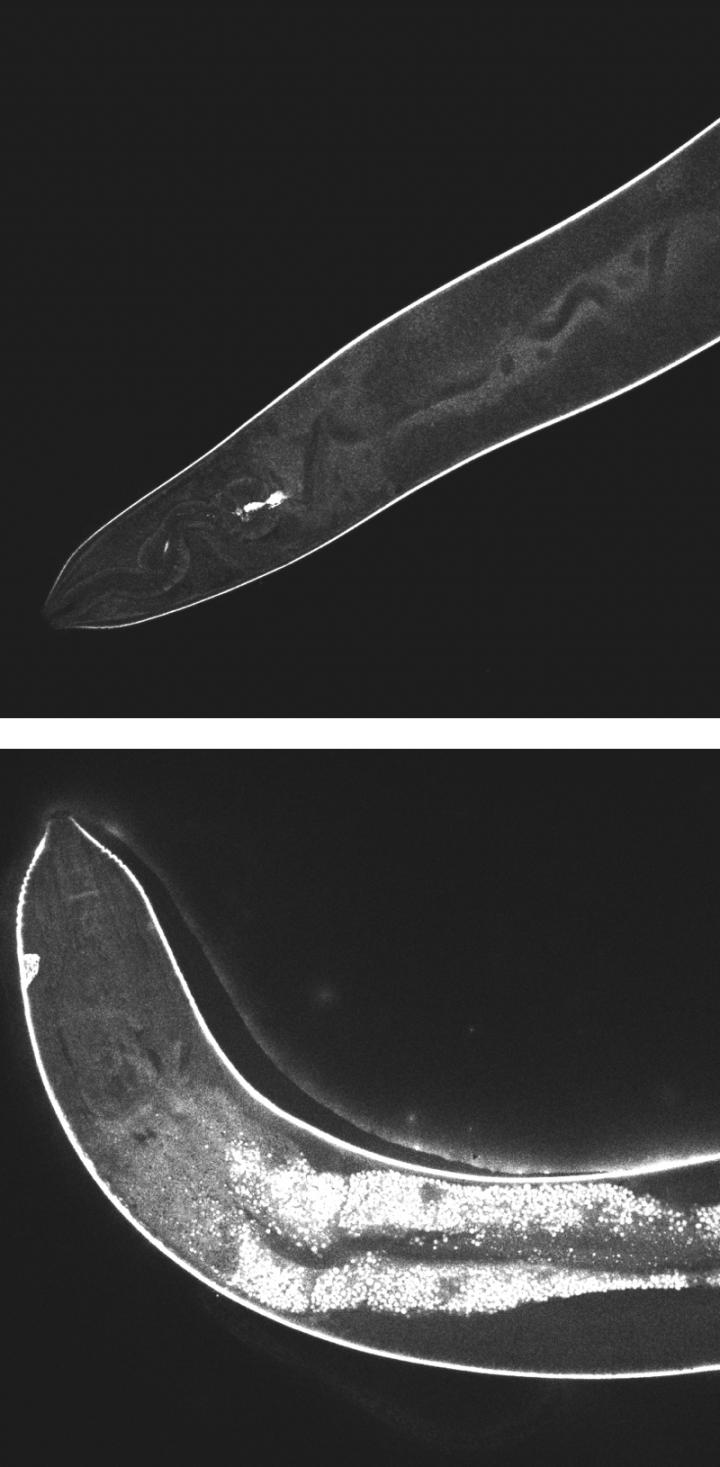

High-resolution confocal images show the effects of light-activated molecular drills on cells inside a worm. Before activation, at top, the injected drills remain dark. At bottom, after 15 minutes of exposure to light, fluorescent signals show widespread damage in the transparent nematodes. The drills developed at Rice University are intended to target drug-resistant bacteria, cancer and other disease-causing cells and destroy them without damaging adjacent healthy cells. (Credit: Thushara Galbadage/Biola University)

The researchers saw different effects in each of the three models. In the worm, C. elegans , the fast motors caused rapid depigmentation as the motors first caused nanomechanical disruption of cells and tissues. In the plankton, Daphnia, the motors first dismembered exterior limbs. In both cases, after a few days, most or all of the organisms died.